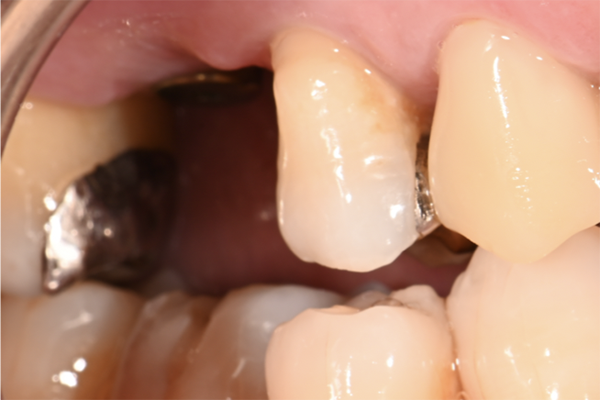

| 主訴 | 歯が痛い |

|---|---|

| 治療内容 | 右上奥歯に対するインプラント治療 (今後右下に対してもインプラント治療を予定) |

| 治療期間 | 6ヶ月 |

| 治療費 | 44万5千円 |

| 治療 リスク | インプラントを埋入したあと3ヶ月程度待ち時間が必要。 その期間は仮歯を使用していただきます。 |